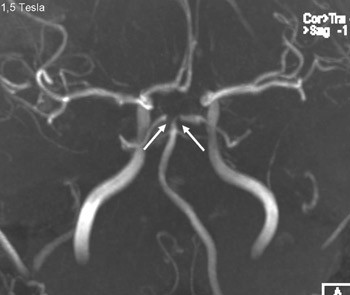

A person in his 20s with known migraine with aura developed infarcts in the right middle cerebral artery and both anterior fields of supply (Figure 1 shows a magnetic tomography diffusion weighted series). Cerebral computed and magnetic tomography with magnetic resonance angiography (MRA) after admission showed normal blood flow and no sign of dissection or vasculitis. Hemicraniectomy became necessary after development of malignant cerebral oedema. MR angiography the first postoperative day showed open arteries (Figure 2 shows an open carotid top (white arrow), normal basilar top (red arrow), and a non-closed circle of Willis, an anatomically normal variant (stars). Testing for illegal drug use, anticardiolipins, anti-nuclear antibodies, neurone antibodies and tumour markers was negative. Transoesophageal echocardiography showed a minimally patent foramen ovale, according to a cardiologic evaluation unlikely to be related to the episode. The patient developed severe brain stem involvement and MR angiography showed narrowing of the posterior branch of the basilar artery (arrows in Figure 3). Arterial vessel spasms were suspected retrospectively. The first suspected vessel spasm, in the right – middle/anterior branch, remained undocumented. The second, in the posterior branch of the basilar artery, was documented postoperatively (arrows in Figure 3). Images of several newly developed infarcts in the posterior circulation are not shown. Three weeks after the hemicraniectomy the angiogram was normalised (Figure 4).